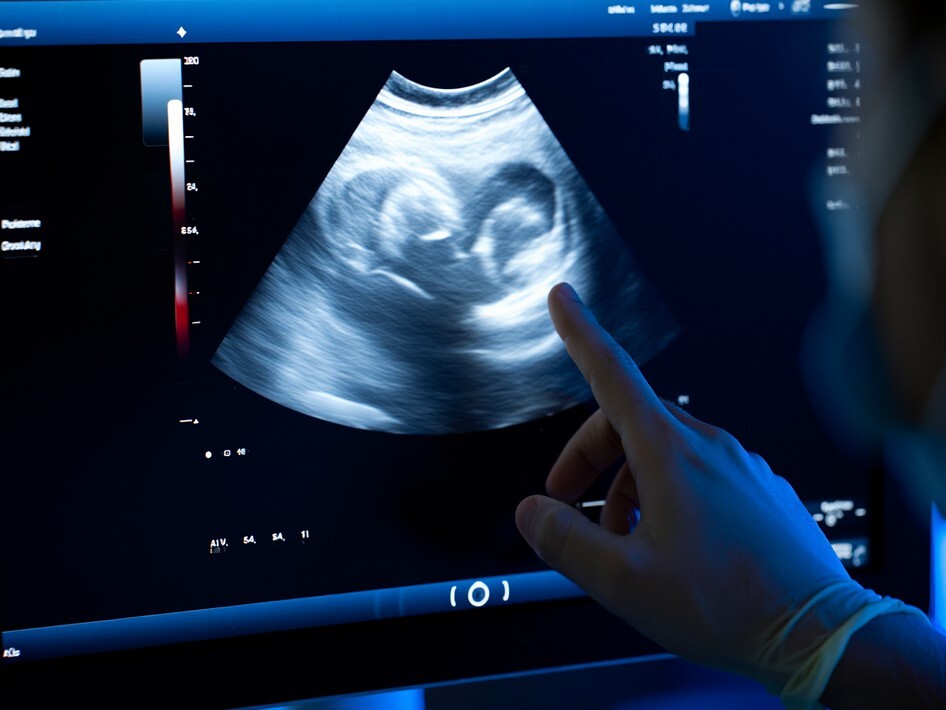

Диагностика кисты яичника на УЗИ

УЗИ — «золотой стандарт» в диагностике, позволяющий точно оценить структуру и тип кисты.

Шаг 2: УЗИ — «золотой стандарт» визуализации

Основа диагностики. Трансвагинальное УЗИ позволяет с высочайшей точностью рассмотреть структуру яичников и самого образования. Иногда его дополняют абдоминальным (через живот) для общей оценки.